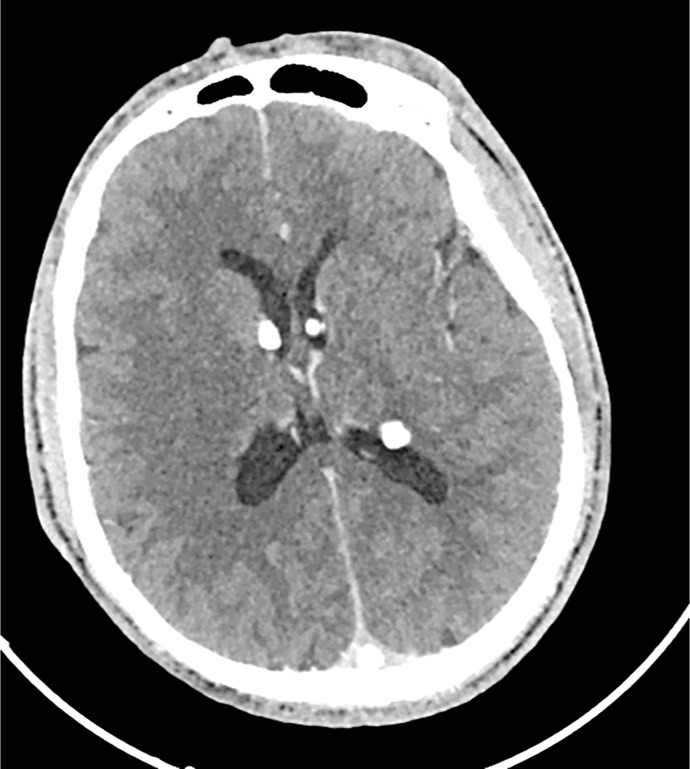

Case presentation: We present a 22-year-old male from rural Tanzania with a 20-year history of intractable, treatment-refractory epilepsy. He also exhibited cutaneous findings, including facial angiofibromas, ash-leaf macules, and a shagreen patch. Brain imaging revealed subependymal nodules, and renal imaging identified angiomyolipomas. Despite the absence of genetic testing, a clinical diagnosis of TSC was made. The patient's condition was further complicated by aspiration pneumonia. Management included anticonvulsant therapy, antibiotics, and supportive care. Multisystem evaluation revealed cystic lung disease and renal involvement, underscoring the need for comprehensive follow-up. This case highlights the diagnostic reliance on clinical expertise and basic imaging in resource-limited settings.